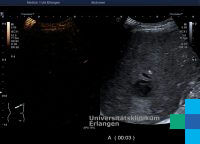

Die Symptome eines Leberabszesses sind meist hohes Fieber, Leberdruckschmerz, Übelkeit und Erbrechen, Gelbsucht und Anämie. Die Diagnose wird mittels Ultraschalluntersuchung und einer CT-Aufnahme gesichert. Die Therapie erfolgt medikamentös (durch hochdosierte Antibiotikagaben), durch eine perkutane Drainage oder durch chirurgische Entfernung der Abszesshöhle eventuell durch eine Segmentresektion. Als Komplikationen eines Leberabszesses gelten eine Sepsis oder Ruptur der Abszesshöhle mit Durchbruch in die freie Bauchhöhle und nachfolgender Bauchfellentzündung.